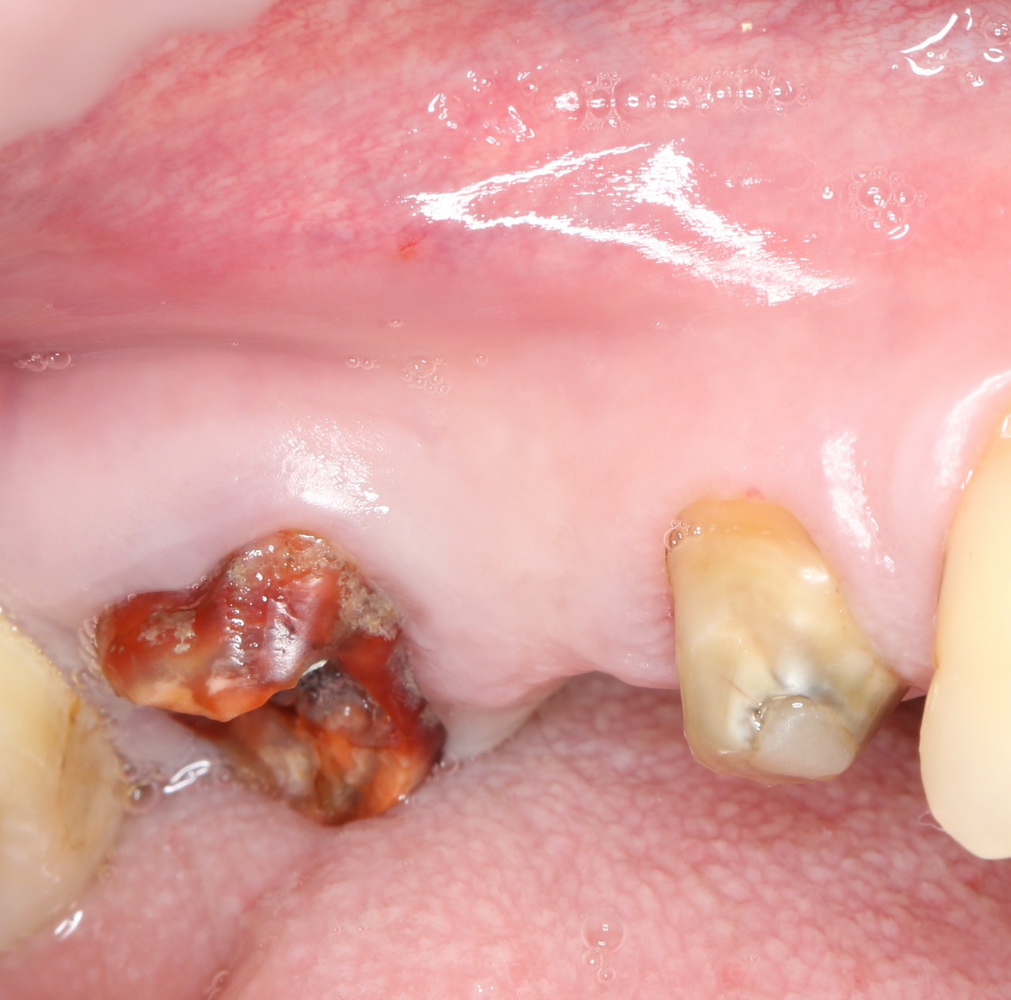

Синуслифтинг и удаление зуба

В некоторых случаях мы можем сочетать операцию синуслифтинга с удалением зуба. Это значительно сокращает сроки имплантологического лечения. Данная методика применяется при невозможности проведения немедленной имплантации одновременно с синуслифтингом.

Необходимым условием для проведения этого вмешательства является стадия ремиссии воспалительного процесса в области удаляемого зуба, отсутствие или небольшие размеры очагов хронического воспаления в прикорневой зоне (рис 49, 50, 51):

Рисунок 49, 50, 51. Проведение операции синуслифтинга одномоментно с удалением зуба: слева – скелетирование стенки верхней челюсти, подготовка к удалению зуба, в центре – лунка удаленного зуба (виден небольшой очаг деструкции костной ткани вследствие хронического периодонтита), справа – заполнение субантральной полости спейсером.